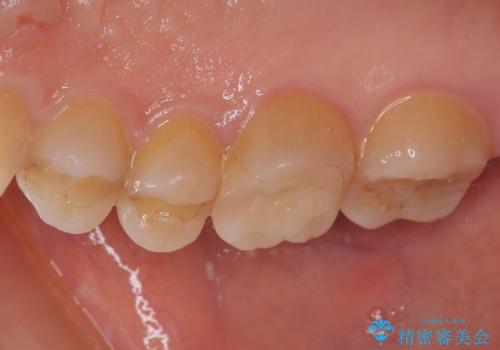

インプラント治療をきっかけに、銀歯を全てセラミックに替えていきました。

人の目を気にせずに、大きく口を開けて笑えるようになりました。